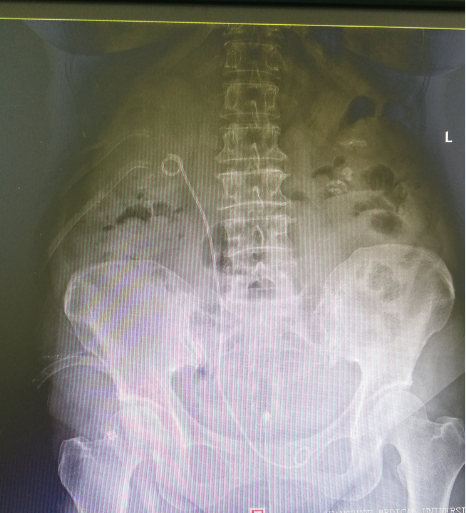

KUB

术前 术后